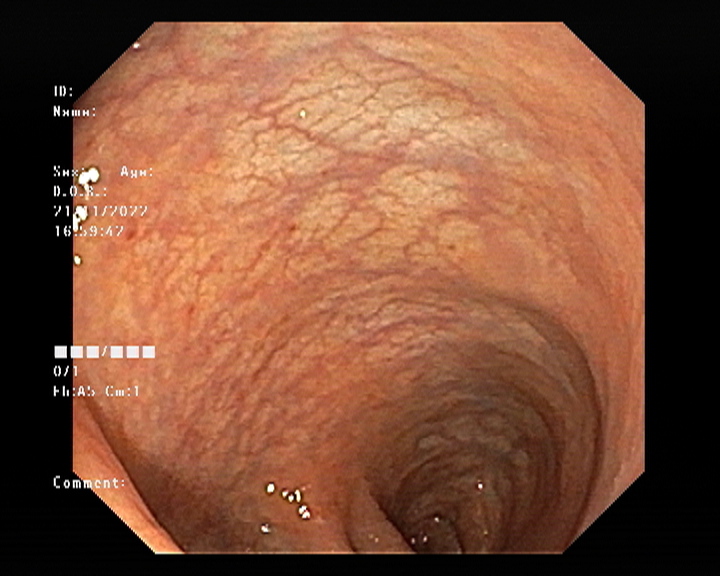

Endoscopy and colonoscopy are safe and accurate procedures used to directly examine the digestive tract and detect the root cause of chronic acidity, GERD, abdominal pain, bleeding, and bowel irregularities. These minimally invasive tests help identify ulcers, inflammation, infections, polyps, strictures, and early cancerous changes.

At Sapphire Gastroenterology Center, modern endoscopic equipment ensures precise diagnosis and, when required, therapeutic intervention during the same procedure. Based on findings, targeted treatment plans are created, including medication, diet guidance, and preventive strategies. Early diagnosis through endoscopy and colonoscopy plays a crucial role in preventing serious complications and improving long-term digestive health.